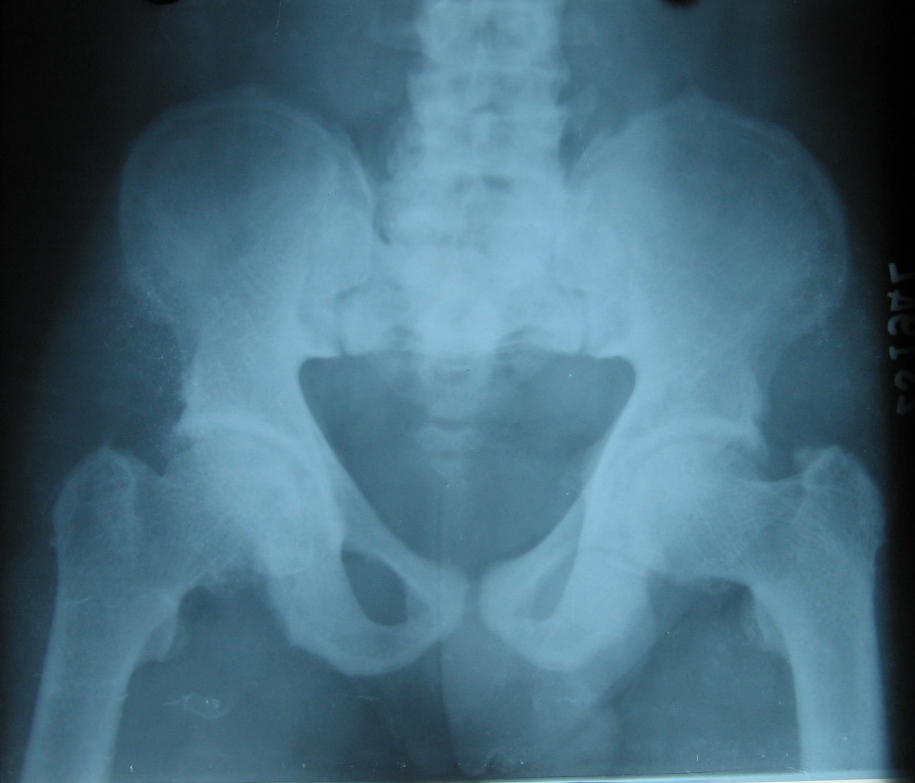

Fig.1 Pelvis A.P